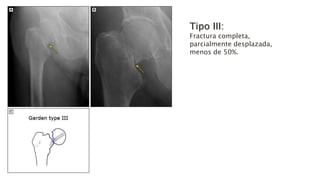

• Tipo III: Fractura completa, parcialmente desplazada, menos de

50%.

Tipo III:

Fractura completa,

parcialmente desplazada,

menos de 50%.